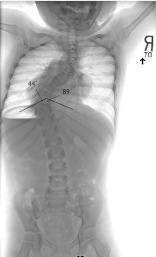

Mehta initially described the Rib Vertebral Angle Difference (RVAD) as a way to predict curve progression in children with infantile idiopathic scoliosis (Fig. 1). This measurement is performed by drawing a line perpendicular to the endplate of the most translated apical vertebrae and then a line down the concave and convex rib at this same level. The angle created on the convexity is then subtracted from that on the concavity to create the RVAD. Mehta found that scoliosis will resolve in 90% of children with a RVAD less than 20° while scoliosis is less likely to resolve when the RVAD is greater than 20°. While RVAD has not been validated in non-infantile EOS, it continues to be used as an indicator of curve severity and progression of deformity. The rib head phase may be used as an adjunct to the RVAD in determining curve progression. The rib phase is determined by the relationship of the rib head and vertebral body at the apex of the curve with overlapping of the vertebral body and the rib head predicting curve progression [12, 13].

Fig. 1.

Rib Vertebral Angle Difference (RVAD). The rib vertebral angle measures the angle formed by a line perpendicular to the endplate of the most apically translated vertebrae and a line drawn down the middle of the concave and convex ribs. The RVAD is the difference between these angles. In the example above, this is 45°. The overlap of the rib heads and the lateral border of the vertebral body indicates significant rotation and a phase II rib